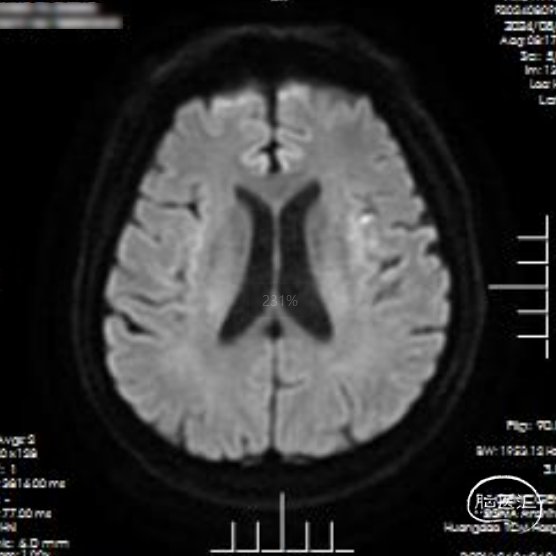

后续完善磁共振检查:DWI示左侧皮层少许点状高信号,MRA示大脑中动脉分支显影良好。